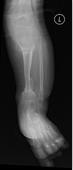

桡骨陈旧性骨折骨不连、畸形

先天性胫骨假关节

肢体短缩延长术,延长9厘米

术前 手术 术后功能恢复良好